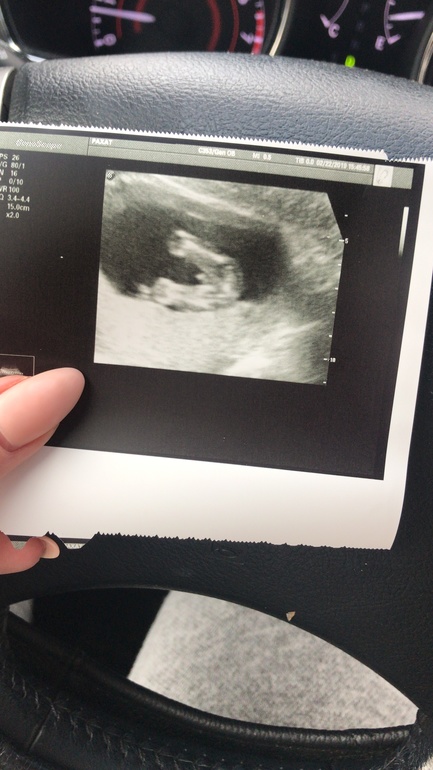

Тогда ждите такую:

Ничо не понятно 😂

Эмм ну куда уж понятнее. Мошонка и писюн )) 26 недель